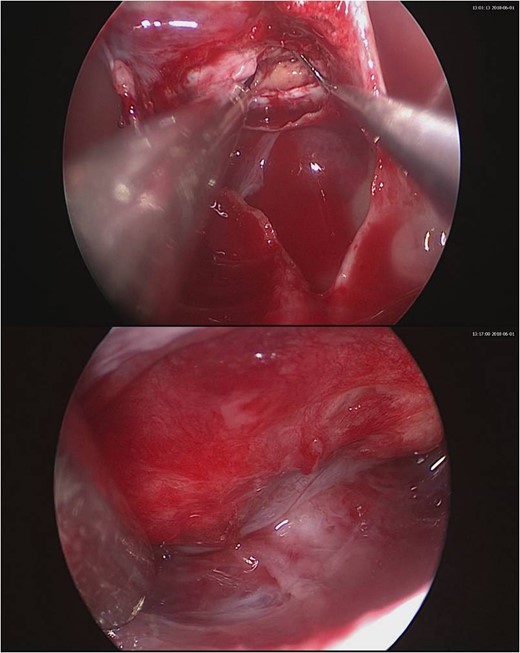

In May 2018, a 28-year-old woman with medical history of sick sinus syndrome and mitral valve prolapse, who just gave birth to a child in April 2018 coming to our Emergency Department with the chief complaint of severe headache and blurred vision for one week. At the Emergency Department, her visual acuity was 0.1 on her right eye and 0.9 on her left eye. Brain CT (computed tomography) scan was checked showing increased soft tissue density over sellar and suprasellar regions, more on the right side. Sellar MRI (magnetic resonance imaging) (Fig. 1) was further arranged which showed a mass with rim enhancement about 2.2 cm ×1.4 cm ×1.2 cm in size located at sella with suprasellar extension with several suspected hemorrhagic foci inside. Under the impression of pituitary apoplexy, she was admitted for further evaluation and management. On admission, her neurological examination showed essentially negative findings except declined right visual acuity; her hormone study showed low level of cortisol (cortisol<1.00 μg/dL) and others were within normal limits. Before surgery, ophthalmologist was consulted again to repeat her ophthalmological examination. The visual acuity of her right eye and left eye improved to 0.8 and 1.0 respectively after the use of steroid. The visual field test showed peripheral defect over the upper visual field of both eyes. Under general anesthesia, she underwent endoscopic endonasal transsphenoidal approach with the removal of tumor and skull base reconstruction. Grossly, the tumor was yellow and soft in consistency and at the end of the procedure, the pituitary gland was well exposed and visible (Fig. 2). After surgery, her vision was subjectively improved; her cortisol level returned to normal (cortisol=16.6ug/dL) and other hormonal data were within normal limits. Histology examination of the tumor (Fig. 3) showed that it composed of spindle to epithelioid cells forming poorly defined lobules and interlacing fascicles, both featuring eosinophilic and oncocytic cytoplasm, with mild nuclear atypia. Immunohistochemically, the neoplastic cells showed TTF-1(+), GFAP(-), EMA(+) Annexin A1(+), and PAS/DPAS(-). Based on the result of histopathology findings and immunohistochemical stains, spindle cell oncocytoma was diagnosed. Before discharge home, her early post-operative sellar MRI (Fig. 4) showed neither residual nor recurrent lesion; she was discharged in a good condition.

Intraoperative pictures. Upper one showing the gross appearance of the tumor. Lower one showing the normal pituitary gland after tumor removal.